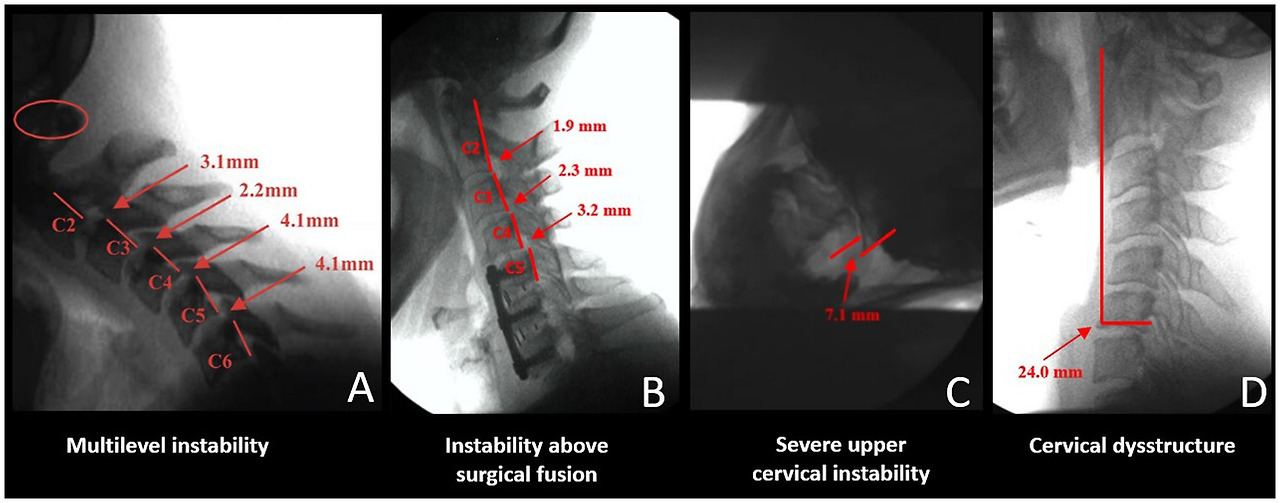

DMX of the spine allows for a continuous and detailed examination of cervical spinal movement and allows unrestricted assessment of C0-C7 motion in multiple dimensions, including the sagittal, rotational, and frontal planes. DMX studies typically include actively moving the head and neck through protraction, retraction, flexion, extension, rotation, and lateral flexion. They show the functional integrity of the ligaments in the cervical spine, specifically the anterior and posterior longitudinal, supraspinous, interspinous, ligamentum flavum, transverse, alar, and facet capsular ligaments. The analysis of over 8,000 DMXs has found 4 common patterns1 (see Figure 7).

1. Extreme overall instability throughout the cervical spine from patients, typically females, with congenital hypermobility syndromes such as Ehlers-Danlos syndrome.

2. Instability above and below the level of prior surgical fusions or degenerative fusions, the latter being more preval‎ent in older males where the degeneration fusions (body fused or fixed the area by bridging osteophytes and disc degeneration) are in the lower segments, commonly C5-C7 and the unstable segments above it.

3. Severe upper cervical instability, especially at the C1-C2 level, can occur from a car accident, head trauma, birth trauma, or high-velocity rotational injury.

4. Cervical dysstructure: breakdown of the cervical curve with a very forward C1.

Figure 7

Figure 7. Common cervical digital motion (fluoroscopy) findings. (A) Multilevel cervical instability. (B) Instability above the level of a surgical or degenerative fusion. (C) Upper cervical instability at C1-C2 facet joints. (D) Cervical dysstructure.

Severe anterior spondylolisthesis is generally recognized when horizontal translation is greater than 3.0–3.5 mm (56). While there are radiographic diagnostic criteria for lower cervical instability and extreme cases of upper cervical instability, especially those involving the transverse ligament where neurologic insult is current or imminent and surgery is warranted, the accepted diagnostic criteria for chronic upper cervical instability not requiring surgery are not so clear-cut (5760). These classification systems are well-suited for medial atlanto-dens instability but do not eval‎uate in-depth lateral posterior LUCI involving the C0-C1 and C1-C2 facet joints and capsular ligaments. Many of these diagnostic criteria involve non-moving and non-weight-bearing imaging. Upright and motion scanning allows changes to be seen between positions and motions. Cervical ligamentous injury is documented when adjacent vertebral alignments are no longer maintained in certain positions or with certain motions.